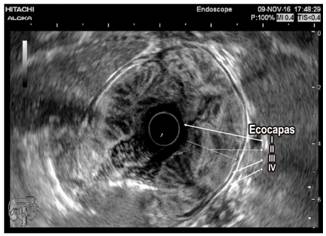

Se solicitaron paraclínicos (hemograma, albúmina, nitrogenados y uroanálisis) y se encontró anemia normocítica, normocrómica, heterogénea (hemoglobina de 11,2 g/dL), albúmina sérica de 2,8 g/dL, con creatinina de 0,8 mg/dL (normal) y uroanálisis sin proteinuria. Dado el hallazgo clínico, paraclínico y endoscópico, se decidió ampliar los estudios con tomografía axial computarizada (TAC) de abdomen, en la que se observan las paredes gástricas engrosadas con compromiso difuso y simétrico marcado de los pliegues gástricos, sin evidencia de lesiones nodulares con un espesor máximo de 53 mm (Figura 1). Se solicitó adicionalmente ultrasonografía endoscópica (USE) gástrica y desde el punto de vista endoscópico se encontraron hallazgos similares a los descritos en la EVDA; y en el tiempo ecográfico se encontró engrosamiento de la pared gástrica dependiente de la ecocapa I y II (mucosa y muscular mucosa, respectivamente), con espacios anecoicos en la ecocapa II, respetando la ecocapa III y IV (submucosa y muscular propia, respectivamente) (Figura 2).

El diagnóstico diferencial gira en torno a otras entidades que engrosen los pliegues gástricos como gastritis linfocítica, síndromes polipósicos, pólipos hiperplásicos, linitis plástica y linfoma, entre otros (Tabla 1). La USE constituye una herramienta útil para el diagnóstico diferencial ya que puede excluir un engrosamiento de origen vascular en el que las biopsias podrían producir complicaciones hemorrágicas importantes, por lo que se recomienda que la USE preceda a la decisión de realizar biopsias en los casos de engrosamiento de los pliegues gástricos; además, apoya el diagnóstico de enfermedad de Ménétrier cuando el engrosamiento se origina en la ecocapa II (Figura 2) 6,7.